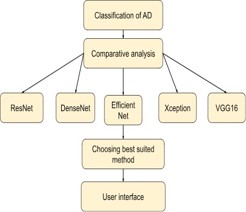

Block diagram

The figure 10 shows the workflow of how the comparative analysis has been carried out to select the best suited model for this case study.

F. Comparative analysis is done for the classification of AD to choose the best suited algorithm for better efficiency and accuracy. EfficinetNetB2 is the best suited method for the classification since it provides peak accuracy about 97.22% and also significantly less loss.